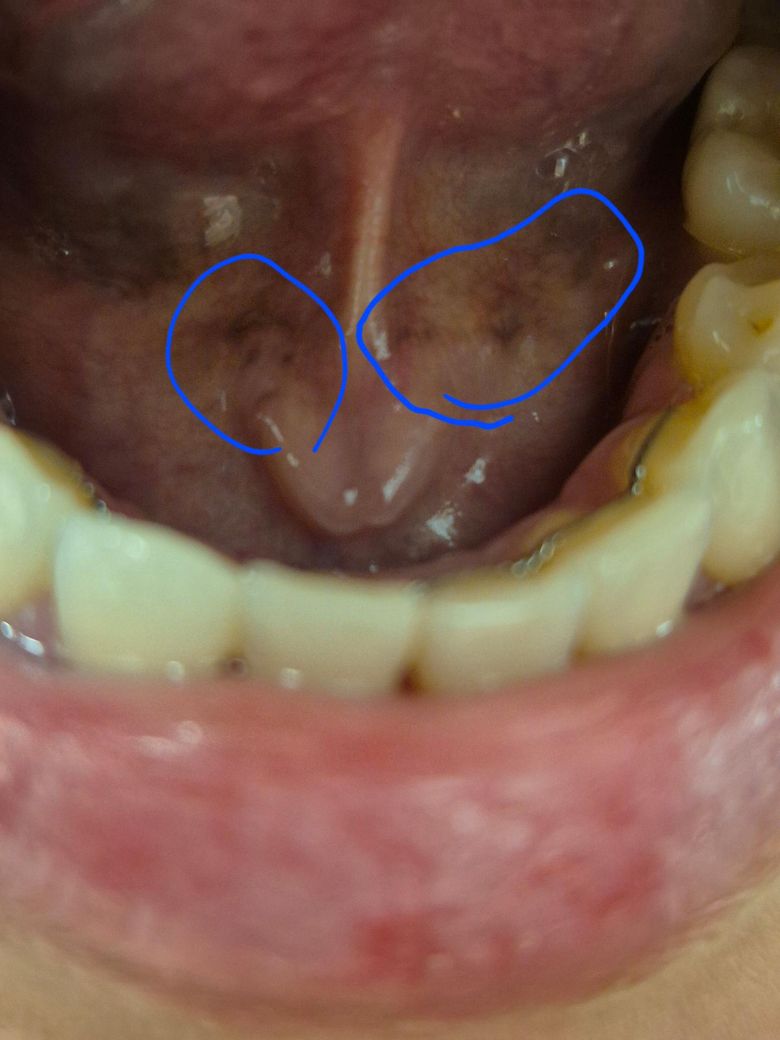

(혓바닥) 혀 밑 색이 이상해요ㅠㅠ 봐주세요

갈색? 흑색? 같은데..심각한건가요?

사진상 혀 밑 점막이 갈색·보라색으로 보이는 것은 비교적 흔한 소견입니다. 이 부위는 혈관이 매우 풍부해 정맥이 비쳐 보이거나 색이 진해 보일 수 있습니다. 특히 설하정맥 확장, 색소 침착, 혈류 변화로 이런 색조가 나타나는 경우가 많고, 통증·궤양·딱딱한 결절이 없다면 심각한 질환 가능성은 낮습니다.

술과 담배는 점막 자극과 색소 침착을 악화시킬 수는 있으나, 이것만으로 암을 의심할 소견은 아닙니다. 다만 최근 색이 급격히 변했거나 한쪽만 국소적으로 짙고 만졌을 때 딱딱하거나, 잘 낫지 않는 상처·출혈·통증이 동반되면 확인이 필요합니다.

진료는 이비인후과나 구강악안면외과(치과병원)로 가시면 됩니다. 대부분은 시진만으로 판단 가능하고, 의심 소견이 있을 때만 추가 검사나 조직검사를 고려합니다. 특별한 치료가 필요 없는 경우가 많고, 경과 관찰을 권하는 경우가 일반적입니다.

현재 사진만으로는 응급하거나 고위험 소견은 보이지 않습니다. 불안하시면 외래에서 한 번 확인받는 정도면 충분해 보입니다.